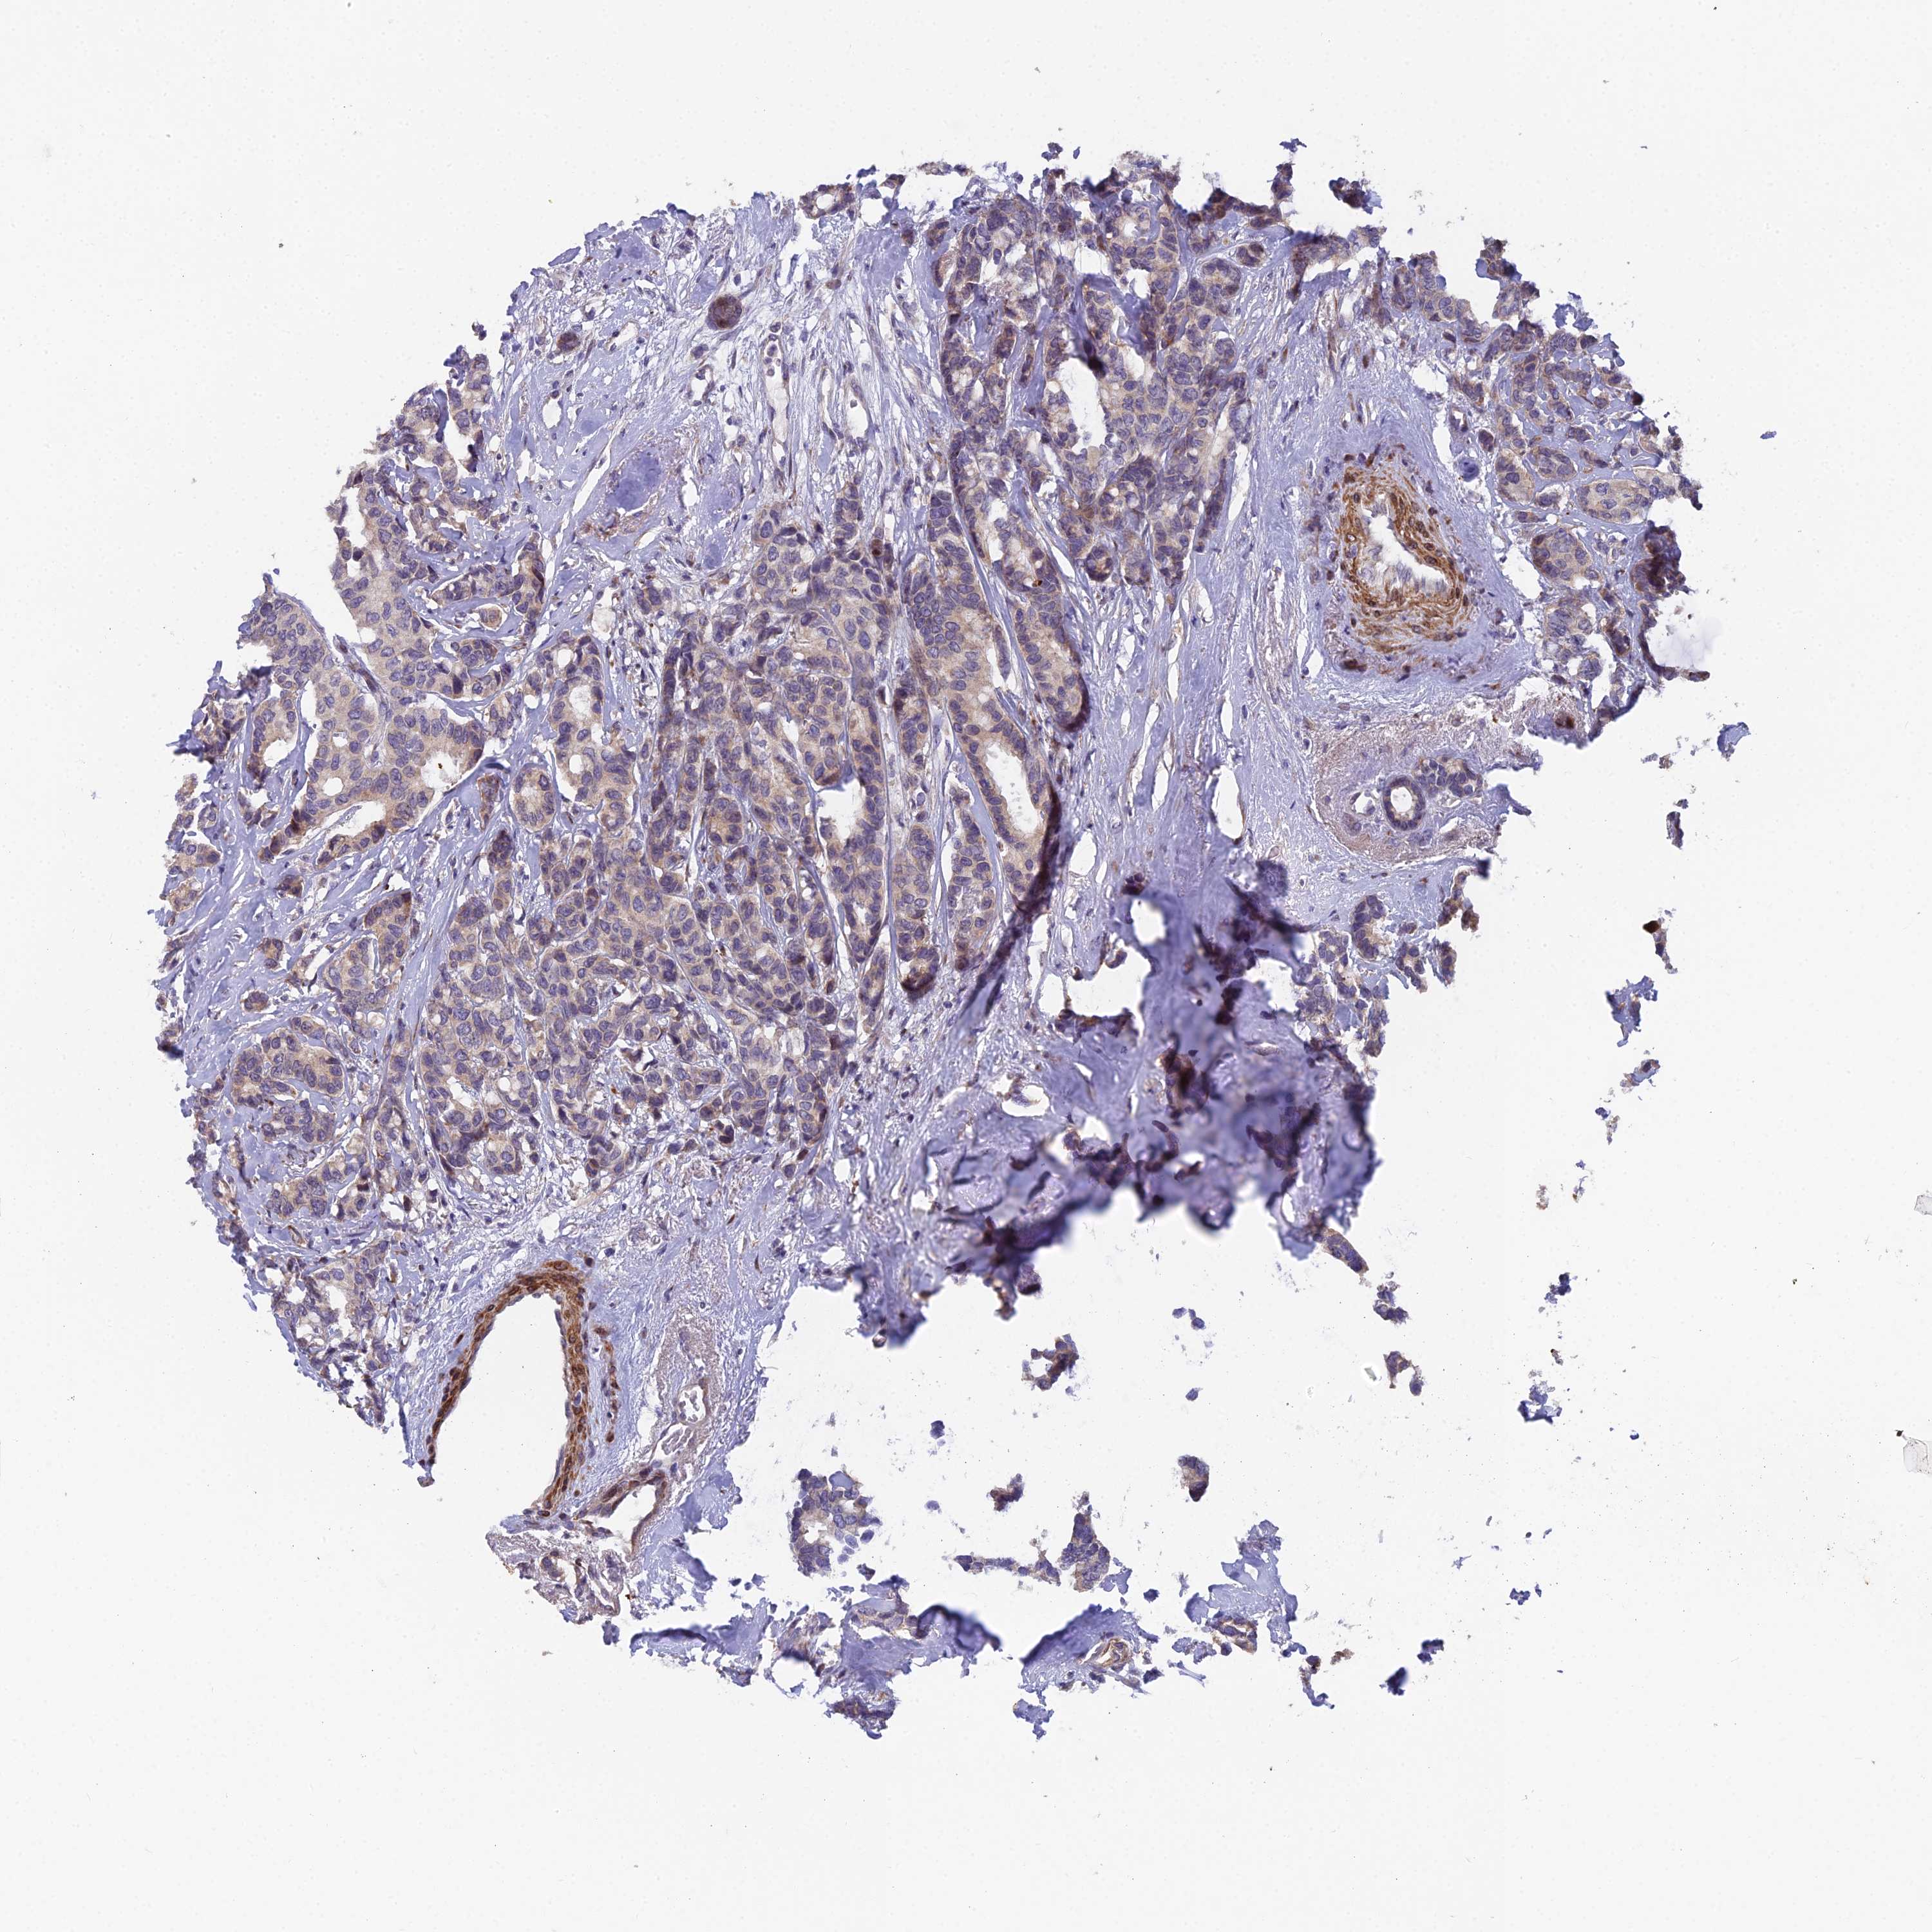

CANCER BREAST CANCER Show tissue menu

BRCA TCGA BRCA VALIDATION PROTEIN EXPRESSION

Breast cancer

Human cancer

RAB28 is not prognostic in Breast Invasive Carcinoma (TCGA)